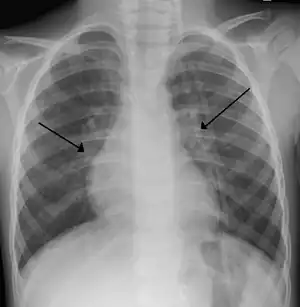

| An X-ray of a child with RSV showing the typical bilateral perihilar fullness of bronchiolitis. | |

Bronchiolitis is usually the result of infection by respiratory syncytial virus (70% of cases) or human rhinovirus (26% of cases).[2][5] Diagnosis is generally based on symptoms.[1][5] Tests such as a chest X-ray or viral testing are not routinely needed.[2][5]

The diagnosis is typically made by clinical examination. Chest X-ray is sometimes useful to exclude bacterial pneumonia, but not indicated in routine cases.[16] Chest x-ray may also be useful in people with impending respiratory failure.[17] Additional testing such as blood cultures, complete blood count, and electrolyte analyses are not recommended for routine use although may be useful in children with multiple comorbidities or signs of sepsis or pneumonia.[6][17]